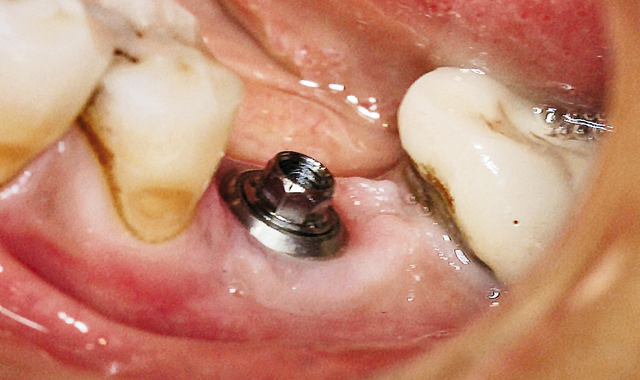

Fig. 15 Zirconia crown.

Fig. 16 Final restoration.